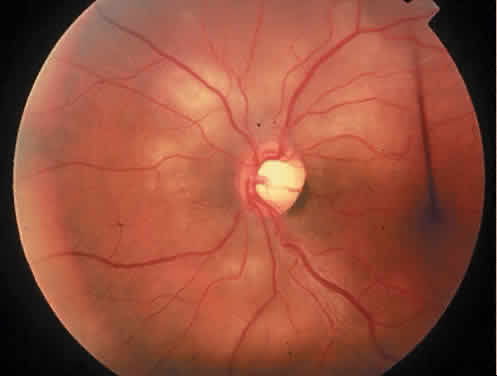

Ophthalmic manifestations of leukemia can be classified into two groups: (1) primary leukemic infiltration of tissues and (2) secondary manifestations affecting the eye. Primary leukemic ocular involvement most commonly affects the retina. Typically, leukemic retinal infiltrates are grayish-white nodules that may be associated with surrounding hemorrhages (Fig. 15).113 Clinical evidence of leukemic choroidal infiltration is rare despite the high (65% to 85%) incidence of choroidal involvement at autopsy.113 Only one of 120 patients in the study by Schachat and coworkers had clinical choroidal involvements. However, the prevalence of choroidal leukemic infiltration is related to the agonal leukocyte count and severity of systemic disease, which may explain the infrequency of clinically apparent choroidal disease. Leukemic infiltration of the choroid diminishes choriocapillaris perfusion, resulting in pigment epithelial ischemia and subsequent breakdown of pigment epithelial barrier and pump functions.117 Some reports have described retinal pigment epithelial hyperplasia and clumping. Histopathology in this situation has shown retinal and choroidal infiltration.118,119 Autopsy studies also have shown infiltrative involvement of the optic nerve in 3.6% of eyes studied.113 Clinically, optic nerve head infiltration may appear as a pale gray swelling of the optic nerve head. Clinical studies have suggested that optic nerve involvement is associated with a high frequency of CNS involvement and a poor prognosis.120,121

Fig. 15. Leukemic infiltrate in the retina in a patient with acute lymphocytic leukemia.